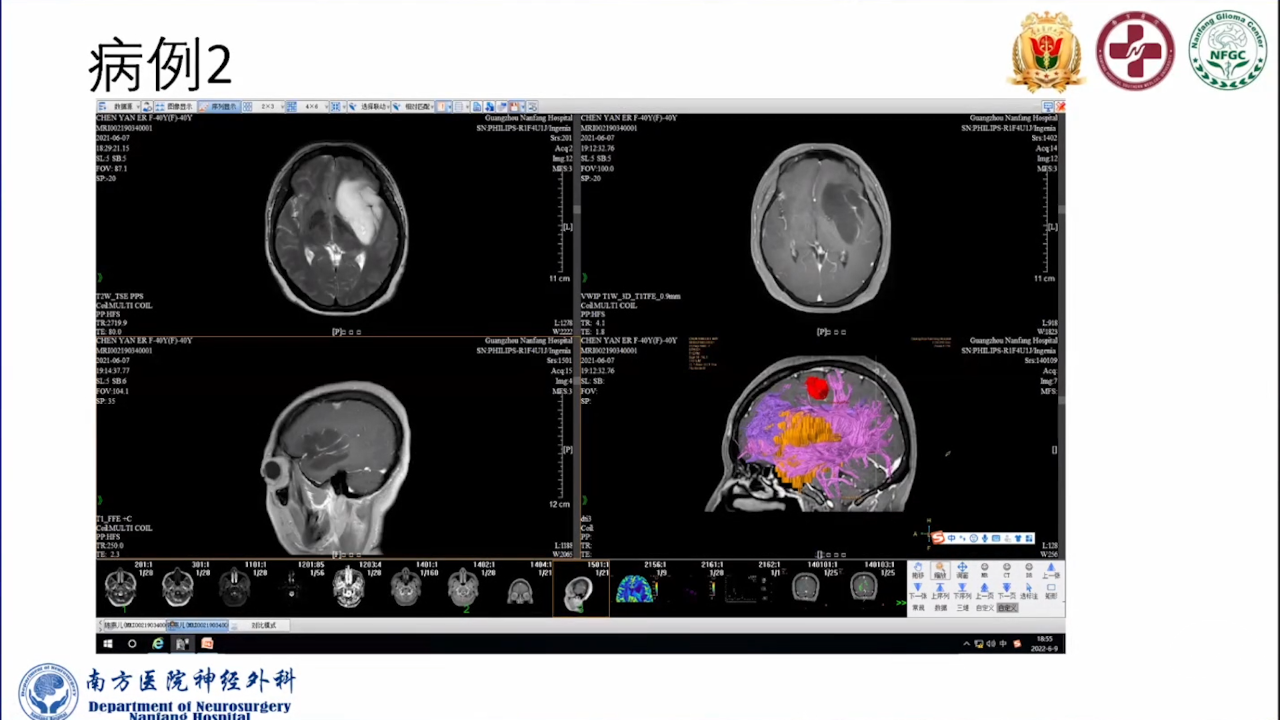

巨大的脑胶质瘤往往破坏皮层功能,推挤白质纤维束,包裹重要供血动脉,正常解剖结构移位。手术切除病变可以挽救患者生命。如果术中确保重要动脉不损伤,并在术前纤维束成像指导下按照解剖结构标志尽可能保留神经纤维束,患者将在获得辅助治疗机会的同时,神经功能也得以逐步恢复,更有利于脑胶质瘤的预后。

会议内容截图